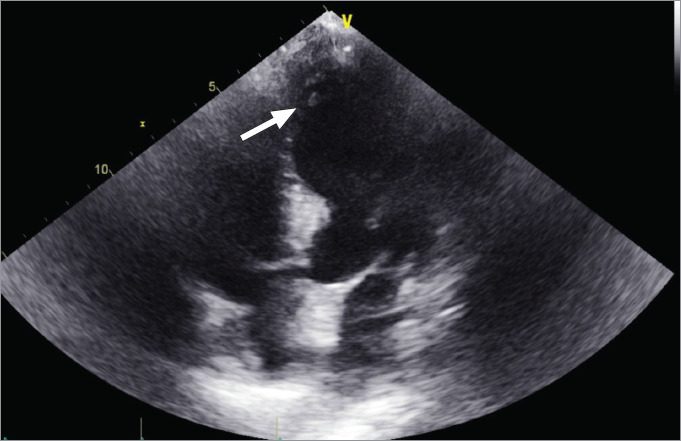

Takotsubo cardiomyopathy (stress cardiomyopathy, or broken-heart syndrome), characterized by reversible left ventricular dysfunction without clinically significant coronary artery obstruction, is rare but has been more commonly reported recently. Esophagogastroduodenoscopy as a cause of takotsubo cardiomyopathy remains exceedingly rare. The case report of an 84-year-old female patient with a complex medical history who had acute stress cardiomyopathy following esophagogastroduodenoscopy, which required prolonged hospitalization and hemodynamic support, is presented. This case emphasizes the importance of recognizing and considering this uncommon pathology and its complications in differential diagnosis. Diagnostic modalities and treatment options for this condition are also discussed.